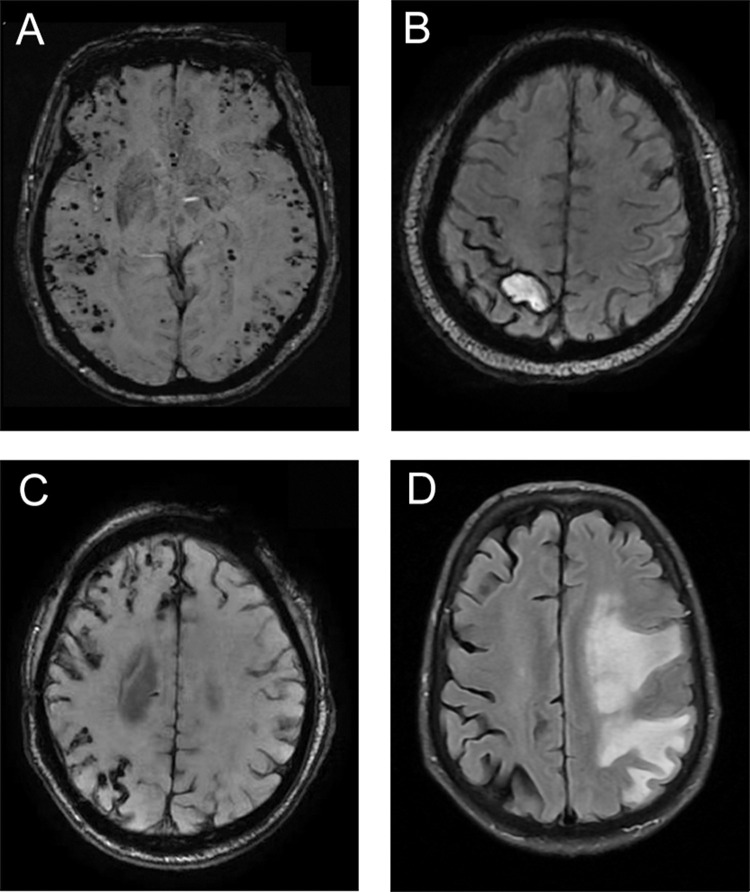

目的:本研究旨在分析一组脑淀粉样血管病相关炎症(CAA-ri)患者的临床表现、实验室结果、神经影像学特征、治疗干预及转归,以加深对这一罕见亚型CAA的认识,提高临床诊断的准确性。方法:对2021年1月至2024年8月郑州大学第一附属医院连续13例符合可能CAA-ri诊断标准并进行评估的患者的临床记录进行系统回顾性分析。结果:研究队列包括13例患者(男性7例,女性6例;平均年龄65.2岁(42 ~ 81岁),主要表现为亚急性发病(53.8%,n=7)。最常见的临床表现是认知障碍(61.5%,n=8),其次是头痛(46.2%,n=6)、癫痫发作(30.8%,n=4)和局灶性神经功能障碍(23.1%,n=3)。所有患者的神经影像学结果均显示不对称白质高信号并伴有皮质-皮质下脑微出血。一部分患者表现为皮质浅表性铁沉着、大叶出血和/或点状急性梗死。在接受腰椎穿刺的9例患者中,5例脑脊液(CSF)压力和蛋白水平升高。所有4例脑脊液阿尔茨海默病生物标志物评估的患者均显示Aβ42和Aβ40水平降低,同时总tau蛋白和磷酸化tau蛋白水平升高。此外,超过70%接受免疫抑制治疗的患者获得了良好的临床结果。结论:临床表现和神经影像学异常是指导临床医生诊断CAA-ri的关键非侵入性标准。CAA-ri患者及时开始免疫抑制治疗可导致良好的结果。

Results: The study cohort comprised 13 patients (7 males, 6 females; mean age 65.2 years, range 42-81), predominantly presenting with subacute onset (53.8%, n=7). Cognitive impairment (61.5%, n=8) emerged as the most frequent clinical manifestation, followed by headache (46.2%, n=6), epileptic seizures (30.8%, n=4), and focal neurological deficits (23.1%, n=3). Neuroimaging findings across all patients demonstrated asymmetric white matter hyperintensities in conjunction with cortical-subcortical cerebral microbleeds. A subset of patients exhibited cortical superficial siderosis lobar hemorrhage, and/or punctate acute infarction. Among the nine patients who underwent lumbar puncture, five showed elevated cerebrospinal fluid (CSF) pressure and protein levels. All four patients assessed for CSF Alzheimer's disease biomarkers showed reduced Aβ42 and Aβ40 levels, alongside elevated total tau and phosphorylated tau levels. Furthermore, over 70% of the patients who treated with immunosuppressive therapy achieved favorable clinical outcomes.